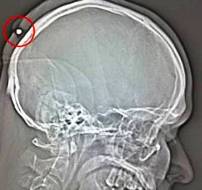

Los médicos dijeron a la policía que habían hallado una bala calibre 22 en la parte posterior de la cabeza del hombre que tiene 35 años de edad, él pensaba que tenía un quiste y se lo quería extirpar.

La herida cicatrizó más tarde cerca de la bala y no fue hasta que el hombre decidió examinar el bulto que tenía en la cabeza debido a los dolores recurrentes que padecía.